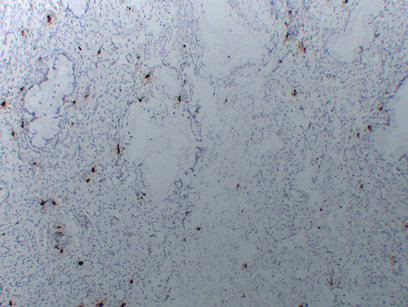

IHC (Immunohistochemisry)

(Immunohistochemical analysis of paraffin-embedded Uterus. 1. Antibody was diluted at 1:200(4 degree overnight). 2. Citrate buffer of pH6.0 was used for antigen retrieval. 3.Secondary antibody was diluted at 1:200(room temperature. 30min).)